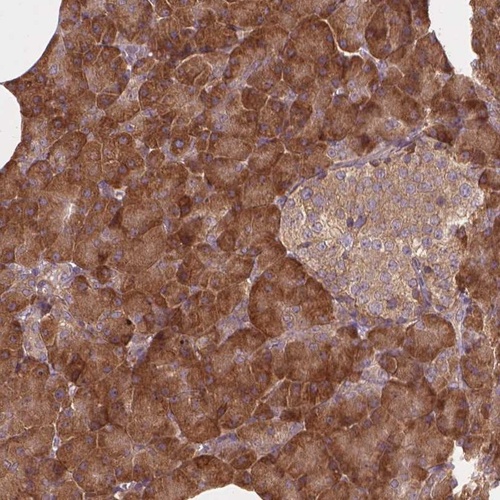

Immunohistochemical staining of human pancreas shows cytoplasmic positivity in exocrine cells.